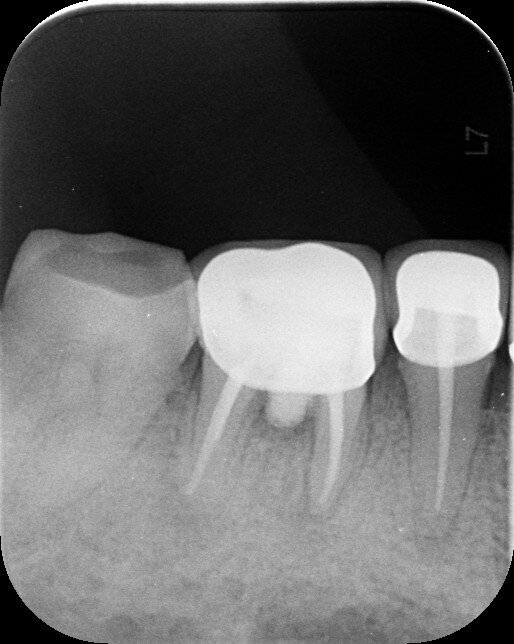

Fig.1a: Pre-op radiograph taken by the referring dentist.

When I had a close look at the preoperative radiograph from the referring dentist (Fig. 1a), I observed that there was insufficient obturation of the mesial canals and almost no obturation of the distal canal. Both roots displayed periapical radiolucency. The clinical examination revealed a Grade I mobility, and the tooth was tender to percussion. The periodontal examination ruled out any pockets and loss of attachment. We took an intra-oral periapical radiograph (Fig. 1b), from which we observed the loss of coronal structure and a large radiolucent area over the furcation area and the periapical area of both the mesial and the distal roots. A CBCT scan of tooth #46 was advised to check for any details that may have been missed in the intra-oral periapical radiograph (Figs. 2a–g). From the CBCT scan, it could be observed that there was inadequate obturation of the distal canal on the horizontal plane, no obturation beyond the middle third in the mesial canals and a breach of the floor of the pulp chamber. The questionable prognosis was explainedto the patient, and written consent was obtained.